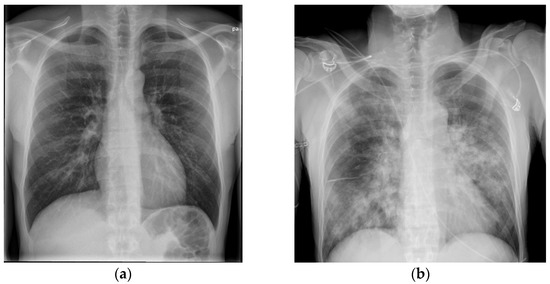

The general practitioner in the Faroe Islands sent him to the radiology department as an out-patient to get a CXR. During the visit to the radiology department, he began to feel lightheaded and nearly fainted. The staff sent him to the emergency department (ED). In the ED, he mentioned that he had felt dyspnoeic and had had productive coughing for 2 days, but that he was feeling better, and the dizziness probably was linked to lack of sleep and exhaustion from the long journey from Colombia to the Faroe Islands. A physical examination revealed a body temperature of 38.9 °C, blood pressure of 134/84 mm Hg, heart rate of 67 beats/min, and oxygen saturation of 98%. The CXR was normal (Figure 1a), and his blood tests showed hemoglobin levels of 7.7 mmol/L, leukocyte levels of 5 × 109/L, and CRP levels of 11 mg/L (Table 1). The patient was a non-smoker and had no history of excessive alcohol consumption. He lived with his wife and children and was a marathon runner in his spare time. The patient was discharged from the ED and advised to contact a doctor if the symptoms worsened or did not get better within a couple of days.

An arterial blood gas test showed a normal pH of 7.40, PaCO2 level of 5.0 kPa, decreased PaO2 level of 9.5 kPa, and elevated lactate level of 3.0 mmol/L. Blood tests showed a hemoglobin level of 8.7 mmol/l, leucocytes level of 1.1 × 109/L, thrombocyte level of 113 × 109/L, creatinine level of 160 µmol/L, and CRP level of 370 mg/L (Table 1). The CXR now showed diffuse bilateral consolidation (Figure 1b). The diagnoses up front were severe community-acquired pneumonia (CAP), septic shock, and ARDS. Disseminated intravascular coagulation (DIC) in progress was first suspected with the symptom of bloody diarrhea in mind, but the blood test results did not suggest severe DIC. The patient was transferred directly to the ICU to get intubated and receive fluid resuscitation, inotrope support, and antibiotic therapy (Table 2).

Figure 1. (a,b) The rapid onset of the severe disease is illustrated here. (a) shows a normal CXR from day 1, 2 days prior to admission. (b) shows a CXR with diffuse consolidation on the day of admission (day 3).